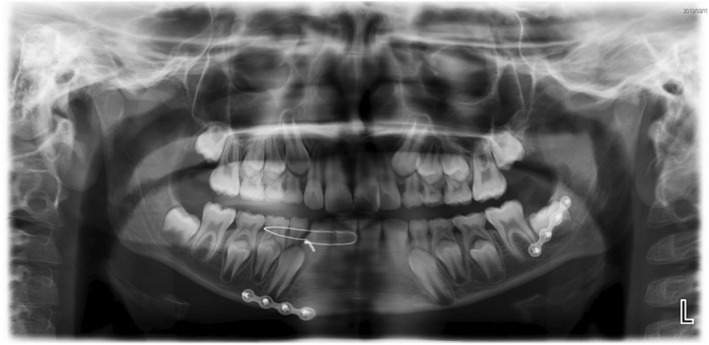

Mandible fractures are relatively uncommon despite the mandible being the most commonly fractured facial bone in the paediatric population. The aetiology of mandible fractures can be categorized as intentional (e.g. as a result of assault, peer-to-peer violence, family violence) or non-intentional (e.g. as a result of falls, motor vehicle crashes, sporting incidents). Peer-to-peer violence affects up to a third of male school aged children in Australia. This case report details the case of a paediatric patient with bilateral mandibular fractures who presented to a general dental practice after an episode of peer-to-peer violence. Clinical examination, radiographic findings and treatment are reported. This paper explores the experience and impact of peer-to-peer physical violence on the individual and his family. A review of the relevant literature is presented. © 2024 Australian Dental Association.

尽管下颌骨是儿科最常见的面部骨骼骨折,但下颌骨骨折却相对并不常见。下颌骨骨折的病因可分为故意伤害(如殴打、同伴间暴力、家庭暴力)和非故意伤害(如跌倒、车祸、体育运动事故)。在澳大利亚,多达三分之一的男性学龄儿童受到同伴间暴力的影响。本病例报告详细介绍了一名患有双侧下颌骨骨折的儿科患者的病例,该患者是在同伴暴力事件后到一家普通牙科诊所就诊的。文中报告了临床检查、放射学检查结果和治疗方法。本文探讨了同伴间身体暴力对个人及其家庭的经历和影响。并对相关文献进行了综述。© 2024 澳大利亚牙科协会。